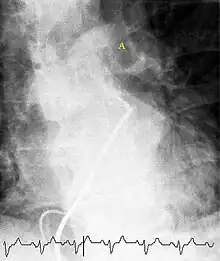

Fluoroscopic pulmonary angiography

Selective pulmonary angiogram revealing clot (labeled A) causing a central obstruction in the left main pulmonary artery. ECG tracing shown at bottom.

Historically, the gold standard for diagnosis was pulmonary angiography by fluoroscopy, but this has fallen into disuse with the increased availability of non-invasive techniques that offer similar diagnostic accuracy.[60]